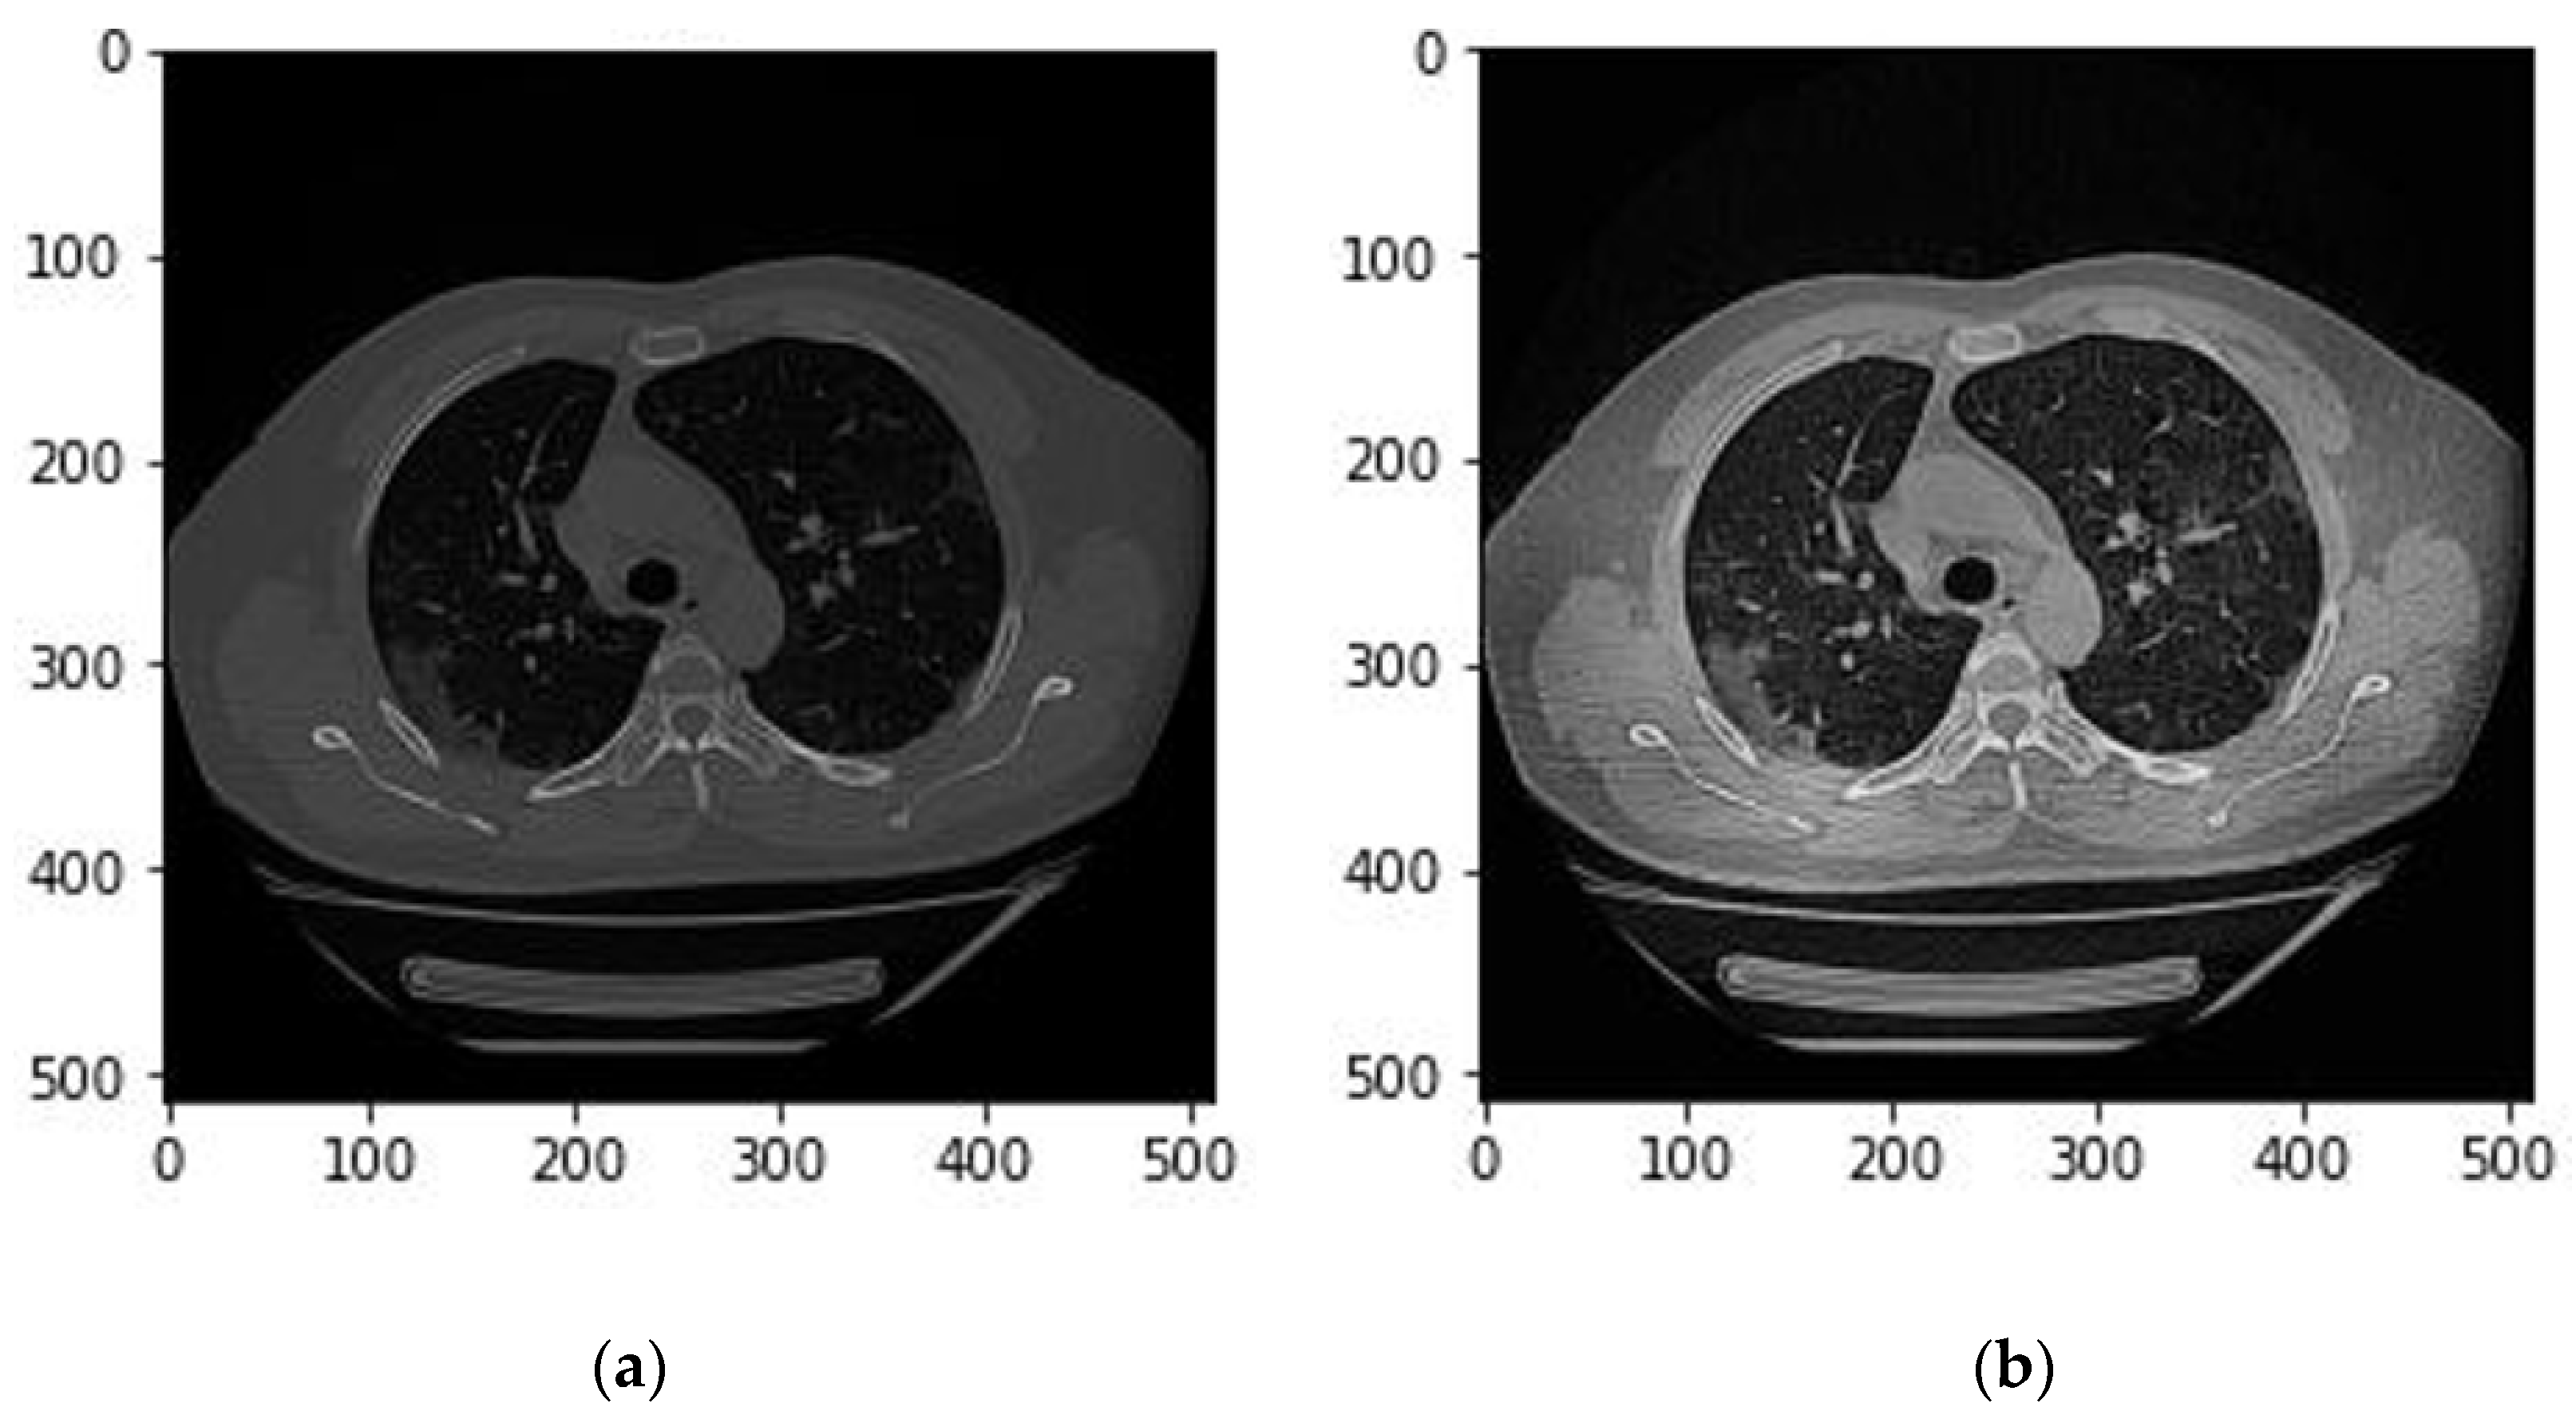

Third, we applied the data augmentation technique to generalize and enlarge the dataset and mitigate overfitting. The main augmentation method adopted in this study is Elastic Transform [15] which is commonly applied in biomedical image analysis. The python library Albumentations [16] was used to perform the Elastic Transform and other affine transformations. Along with the elastic Transform, we also applied horizontal flip, Random rotate, and vertical flip. Figure 1 demonstrates changes of a CT slice after applying an augmentation method in this study.

Figure 1. An example of applying an augmentation method. (a) The original image (b) After applying an augmentation method.